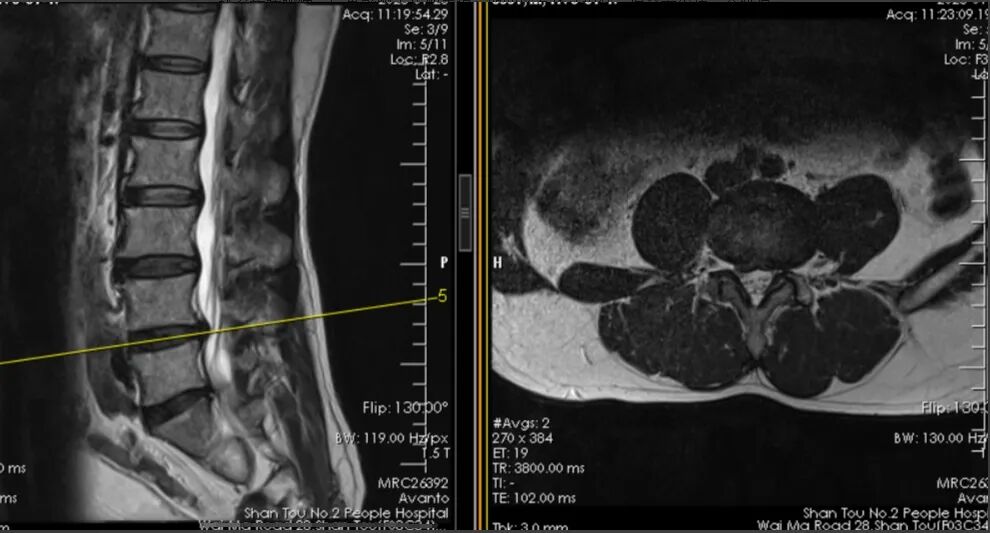

术前MR